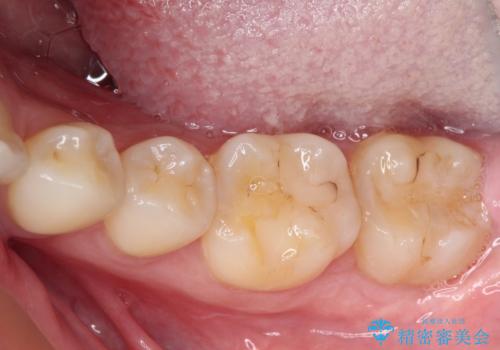

- 左下の奥歯が、冷たいものを食べるとしみて、舌で触るとザラザラすることが気になり来院された患者様です。

以前他院で治療したCR(樹脂の材料)が劣化し、その隙間から冷たいものがしみている可能性が高いことがわかりました。

嚙み合わせの力が強いため、再びCRやセラミックインレーによる修復を行っても割れてしまう可能性が高いので、

ゴールドインレーによる修復を行うこととしました。